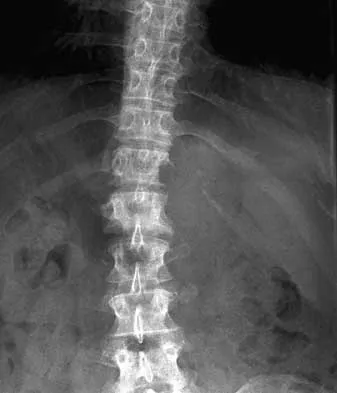

A 44-year-old woman has had lower extremity dysesthesias, urinary incontinence, and has been unable to walk for the past 2 days. She reports no pain or history of trauma. She notes that 3 weeks ago she missed work for 2 days because of back pain, but it resolved with rest. Examination shows decreased or absent sensation below the knees, no motor function below the knees, and decreased rectal tone. Catheterization results in a postvoid residual of 2,000 mL. Plain radiographs and MRI scans without contrast are shown in Figures 1a through 1d. What is the next most appropriate step in management?

Explanation

The patient has had a clear and sudden onset of a profound neurologic deficit. The radiographic studies suggest a lesion in the conus medullaris that appears to be intradural and intramedullary. MRI, with and without contrast, will best evaluate this mass further. The addition of gadolinium allows further evaluation of vascularity and the extent of the lesion. Eichler ME, Dacey RG: Intramedullary spinal cord tumors, in Bridwell KH, Dewald RL (eds): The Textbook of Spine Surgery, ed 2. Philadelphia, PA, Lippincott-Raven, 1997, vol 2, pp 2089-2116.